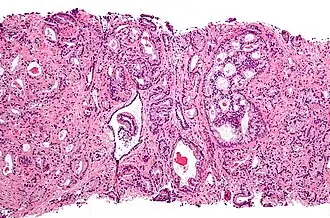

Adénocarcinome prostatique

Adénocarcinome prostatique- Adénocarcinome ; tissus indifférenciés

Anatomopathologie

Le cancer entreprend la portion périphérique de la glande, au contraire de l'hypertrophie prostatique bénigne qui intéresse la zone centrale, périurétrale.

Score de Gleason

La structure tissulaire des cancers de la prostate varie des formes différenciées (cellules cancéreuses ressemblant aux cellules saines), dite de grade 1, aux formes les moins différenciées (cellules cancéreuses présentant beaucoup de caractères atypiques par rapport aux cellules saines), dite de grade 5.

Plusieurs grades peuvent se rencontrer au sein d'un même tissu. Le score de Gleason est calculé de la façon suivante : on additionne les deux grades les plus représentés de la tumeur. Le premier chiffre représentant le score du contingent le plus représenté. Ainsi 4+3 est plus péjoratif que 3+4

Si la somme est de 6 ou moins, le cancer est dit bien différencié, donc de meilleur pronostic ; 7 : le cancer est moyennement différencié ; 8 ou plus : le cancer est peu différencié, donc de moins bon pronostic.